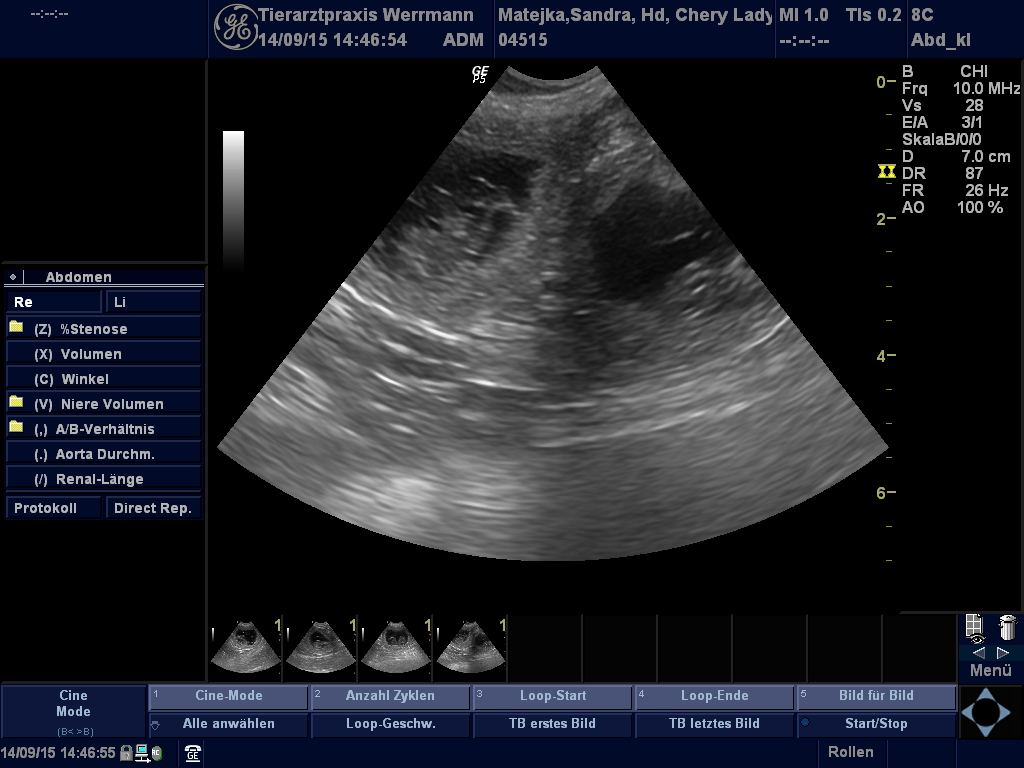

Ultraschallbilder